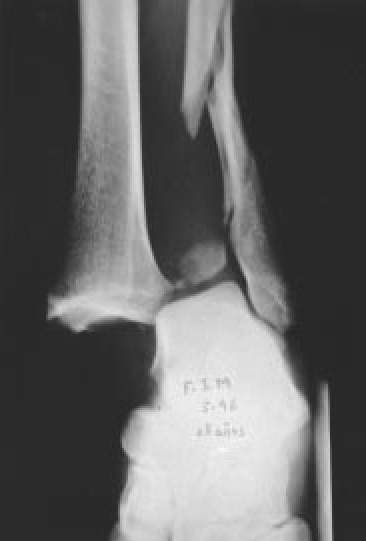

Fig. 10.: Fractura-luxación de tobillo tipo C